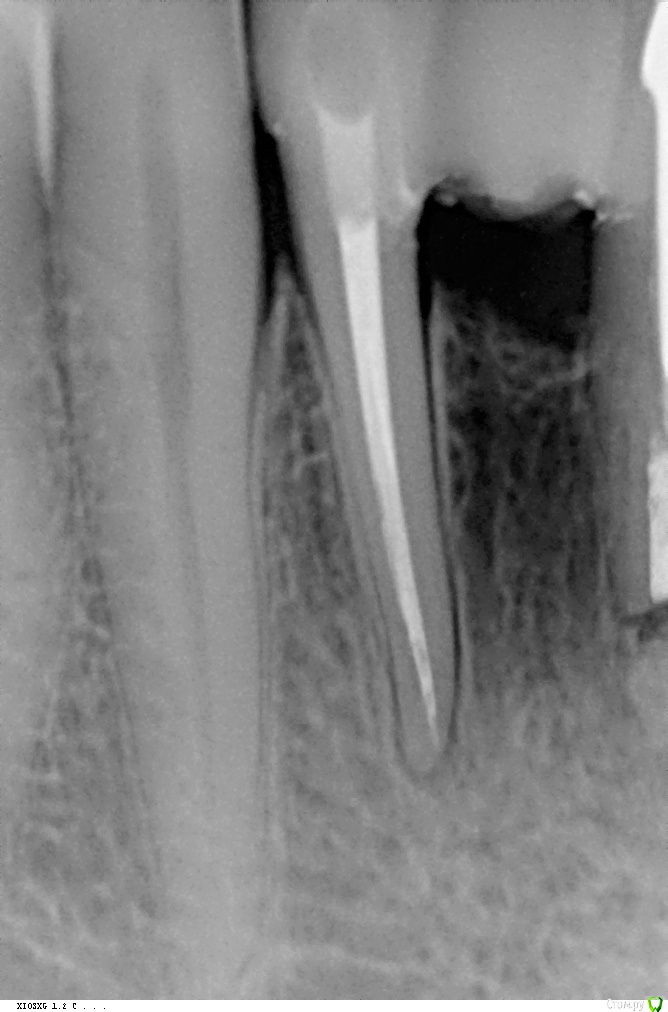

Adonisaktiv Опубликовано 7 октября, 2018 Поделиться Опубликовано 7 октября, 2018 Здравствуйте. У меня очень сложная ситуация. В начале сентября решил поменять зубной мост на передних зубах на нижней челюсти. Мост стоял лет 30 (мне 50). Когда устанавливали первый мост, поставили его на здоровые зубы. Затем лет через десять просверлили коронки и депульпировали зубы. И вот решил я воспользоваться услугами частной клиники и начал делать новый мост. Один из зубов, на которм стояла старая коронка стали лечить. прочистили каналы и поставили новую пломбу. Затем изготовили временную коронку и установили. Сейчас постояная ноющая боль в этом зубе. Стоматолог предлагает удалить этот зуб! Огромная просьба дать консультацию по этому зубу! Заранее большое спасибо!!!Фото прилагаю Ссылка на комментарий

Adonisaktiv Опубликовано 11 ноября, 2018 Автор Поделиться Опубликовано 11 ноября, 2018 Вот пожалуйста. Тока это до установки временной коронки. То есть вопрос можно на эти зубы ставить метвллокерамику. На них давно резекцию делали. Ответьте скорее! 1 Ссылка на комментарий